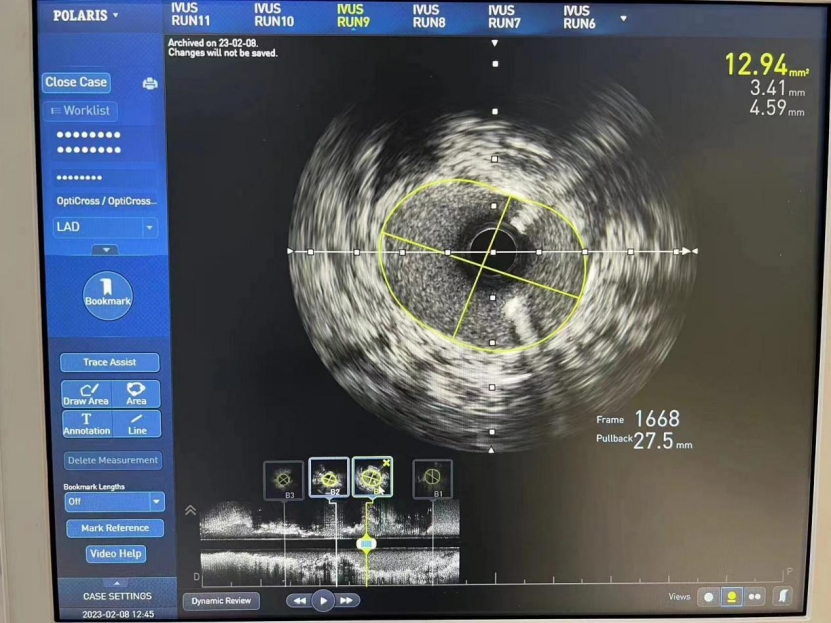

LM

MSA 最小支架腔内面积 12.94mm²

LAD

MSA 最小支架腔内面积 7.0mm²